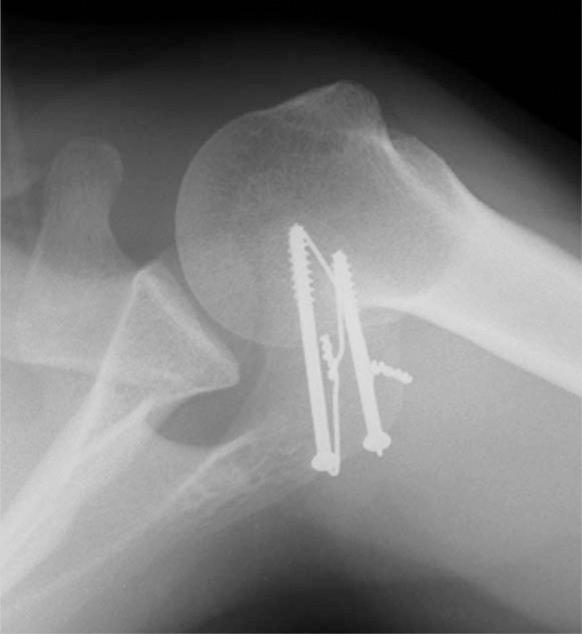

Os acromiale as a cause for shoulder pain in a competitive swimmer: a case report.

Sports Health. 2009 Mar;1(2):121-4. doi: 10.1177/1941738108326705.